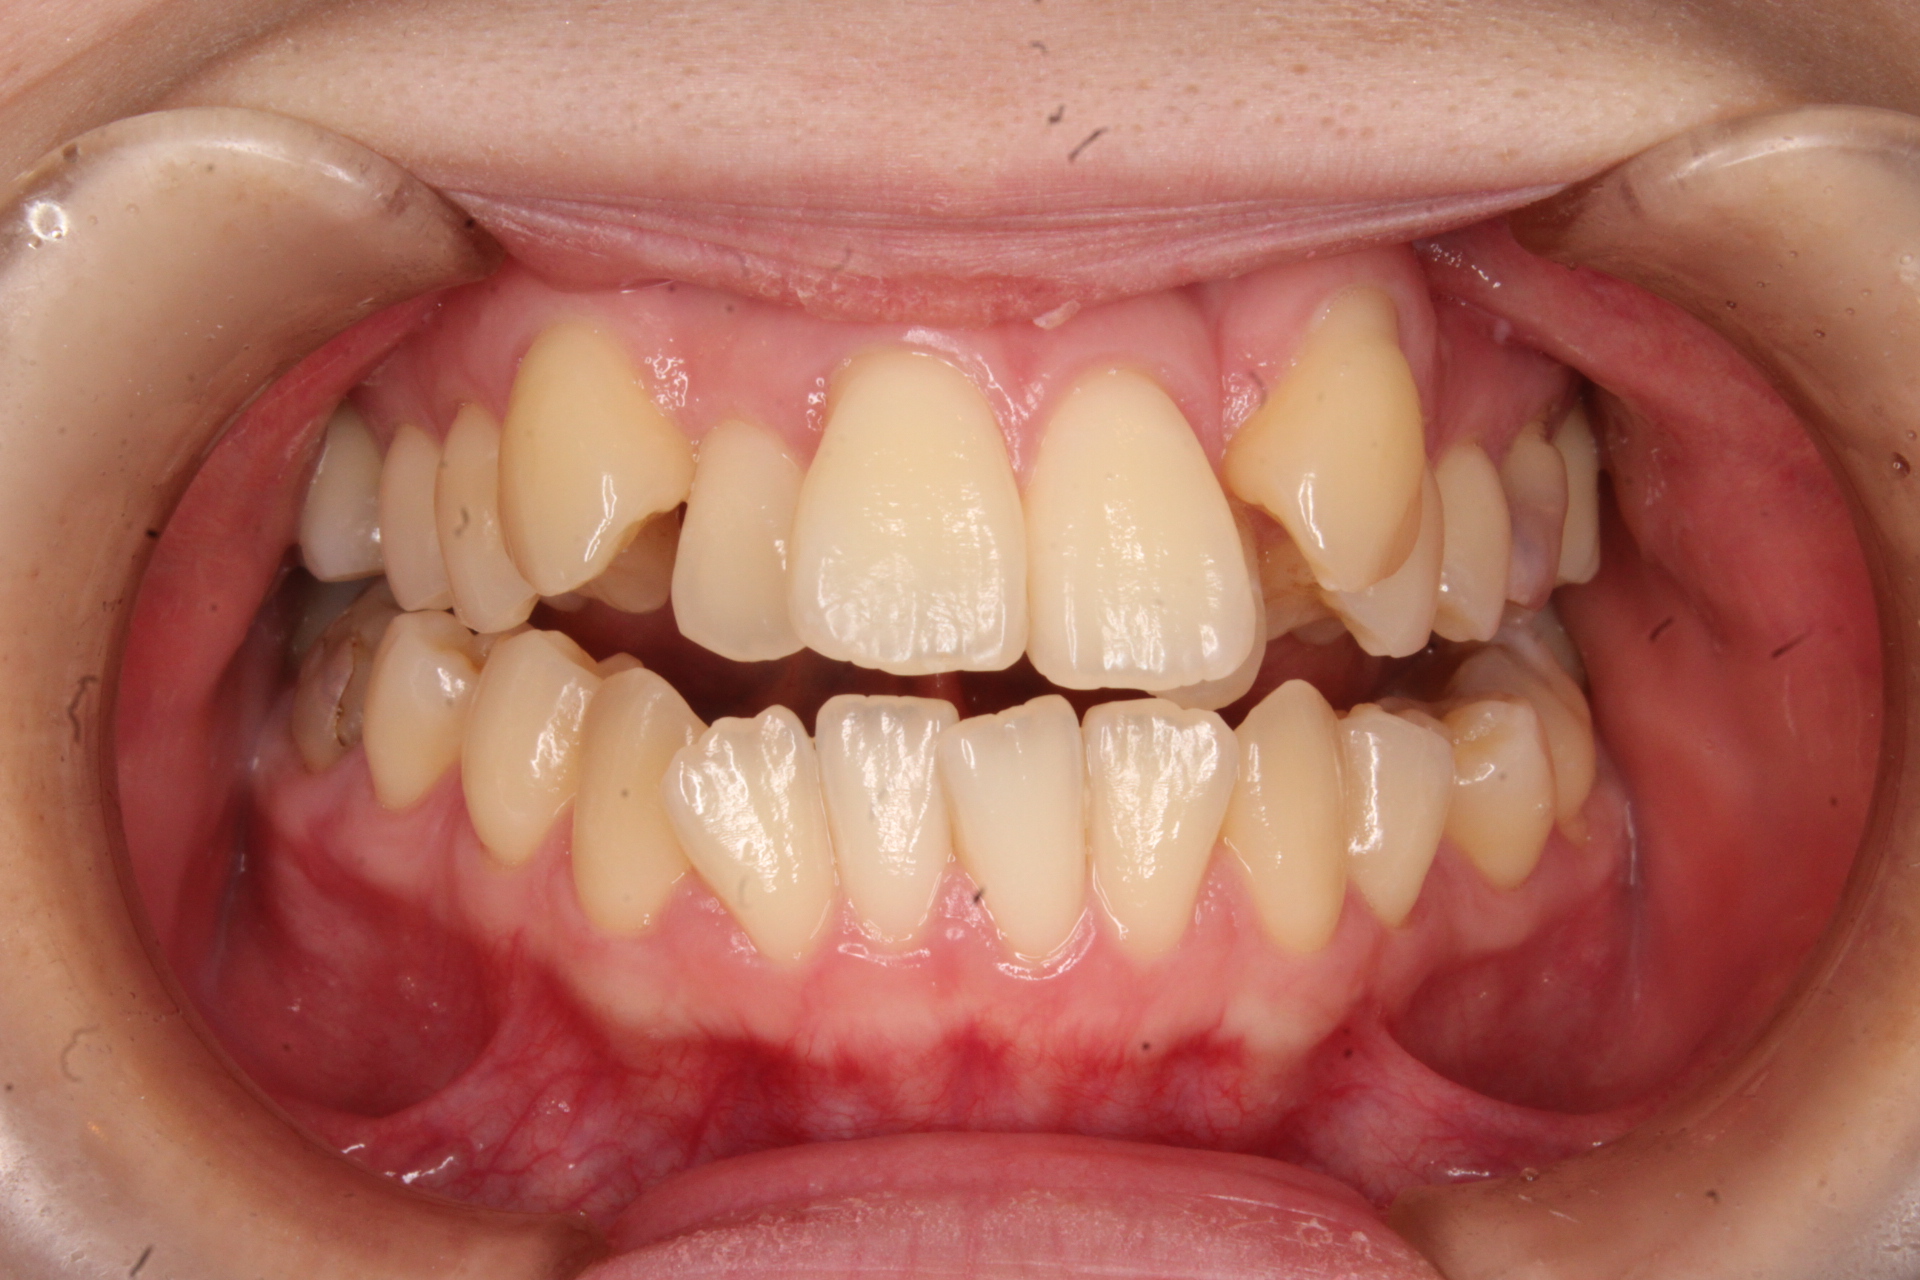

矯正 初診

Before

矯正 終了時

After

叢生・八重歯を治したい!

主訴 【主訴】前歯部の叢生を改善したい 【診断・症状】過蓋咬合・叢生・歯肉退縮

治療費用 検査・診断:38,500-/裏側矯正治療:1,320,000-(※全て税込)

治療期間 約1年9か月(21回)

抜歯 有(上4,4)

矯正の装置 裏側矯正(舌側矯正)

副作用、リスク 歯肉退縮・歯根吸収・疼痛・咬合の違和感・装置の違和感・正中のズレ